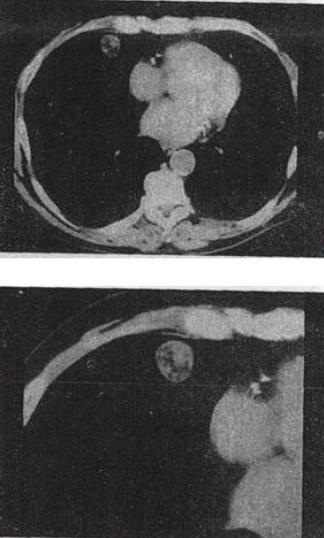

单项选择题 患者女,71岁,咳嗽,咳痰,胸部隐痛2个月余,结合影像学检查,最可能的诊断是()。

A、肺癌

B、肺结核

C、肺错构瘤

D、结节病

E、肺转移瘤

• C